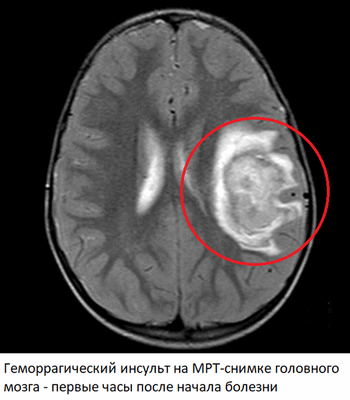

Геморрагические инсульты или внутримозговые кровоизлияния составляют 15% всех острых нарушений мозгового кровообращения. Непосредственная причина - разрыв артерий головного мозга, ослабленных атеросклеротическими изменениями и повышением артериального давления. Гипертоническая болезнь - один из главных факторов риска геморрагического инсульта.

Признаки геморрагического инсульта на МРТ головного мозга

Изменения на МРТ после геморрагического инсульта появляются на снимках уже через несколько минут после начала болезни. Магнитно-резонансная томография имеет отдельный режим (SWI) для обнаружения крови, что позволяет с высокой точностью установить факт наличия кровоизлияния в головной мозг. Причем расположение, объём и протяженность гематомы имеют прогностическое значение. В сосудистом режиме обнаруживаются артерии головного мозга, с явными признаками атеросклероза.

Через 1-2 часа после кровоизлияния кровь сворачивается, из-за чего соответствующие изменения начинают появляться и на снимках, сделанных в обычных режимах. Область гематомы изменяется, вокруг нее появляется кольцо, обусловленное отеком мозга и нарушением кровообращения. В центре - неоднородная масса, соответствующая сгустку крови. Такая картина сохраняется на протяжении нескольких дней или даже недель и соответствует тяжелому поражению мозга. В некоторых случаях возможно проведение хирургического удаления гематомы, однако на практике из-за высокой летальности (40-70%) и тяжелого состояния пациента такие операции проводятся редко.